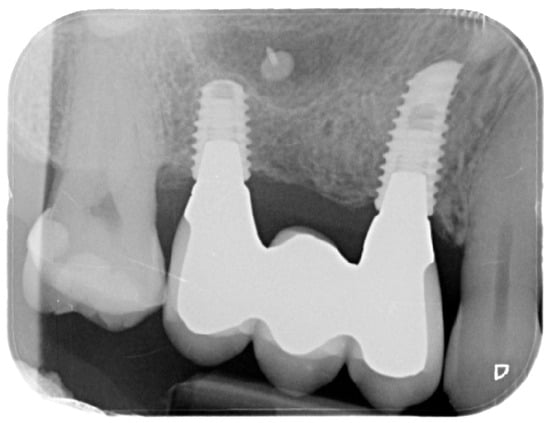

Figure 8. Postoperative intraoral X-ray.

For the evaluation of the mesial and distal MBL, intraoral digital radiographs were taken using the long-cone paralleling technique with the central beam directed to the alveolar crest. Periapical radiographs were taken at the delivery of the prosthesis and after 1 year of prosthetic loading (T2). The mesial and distal MBL, i.e., the distance between the top of the implant shoulder and the first visible bone-to-implant contact, were measured at the mesial and distal aspect with a 10–15× magnification using an image analysis programme (ImageJ v 1.49, NIH, Bethesda, MA, USA). The length of the implant was used as known measure for the calibration and determination of the exact magnification and distortion of the images. All measurements were performed by two examiners to the nearest 0.1 mm. In case of disagreement, the evaluation was re-done and results discussed until an agreement was found.